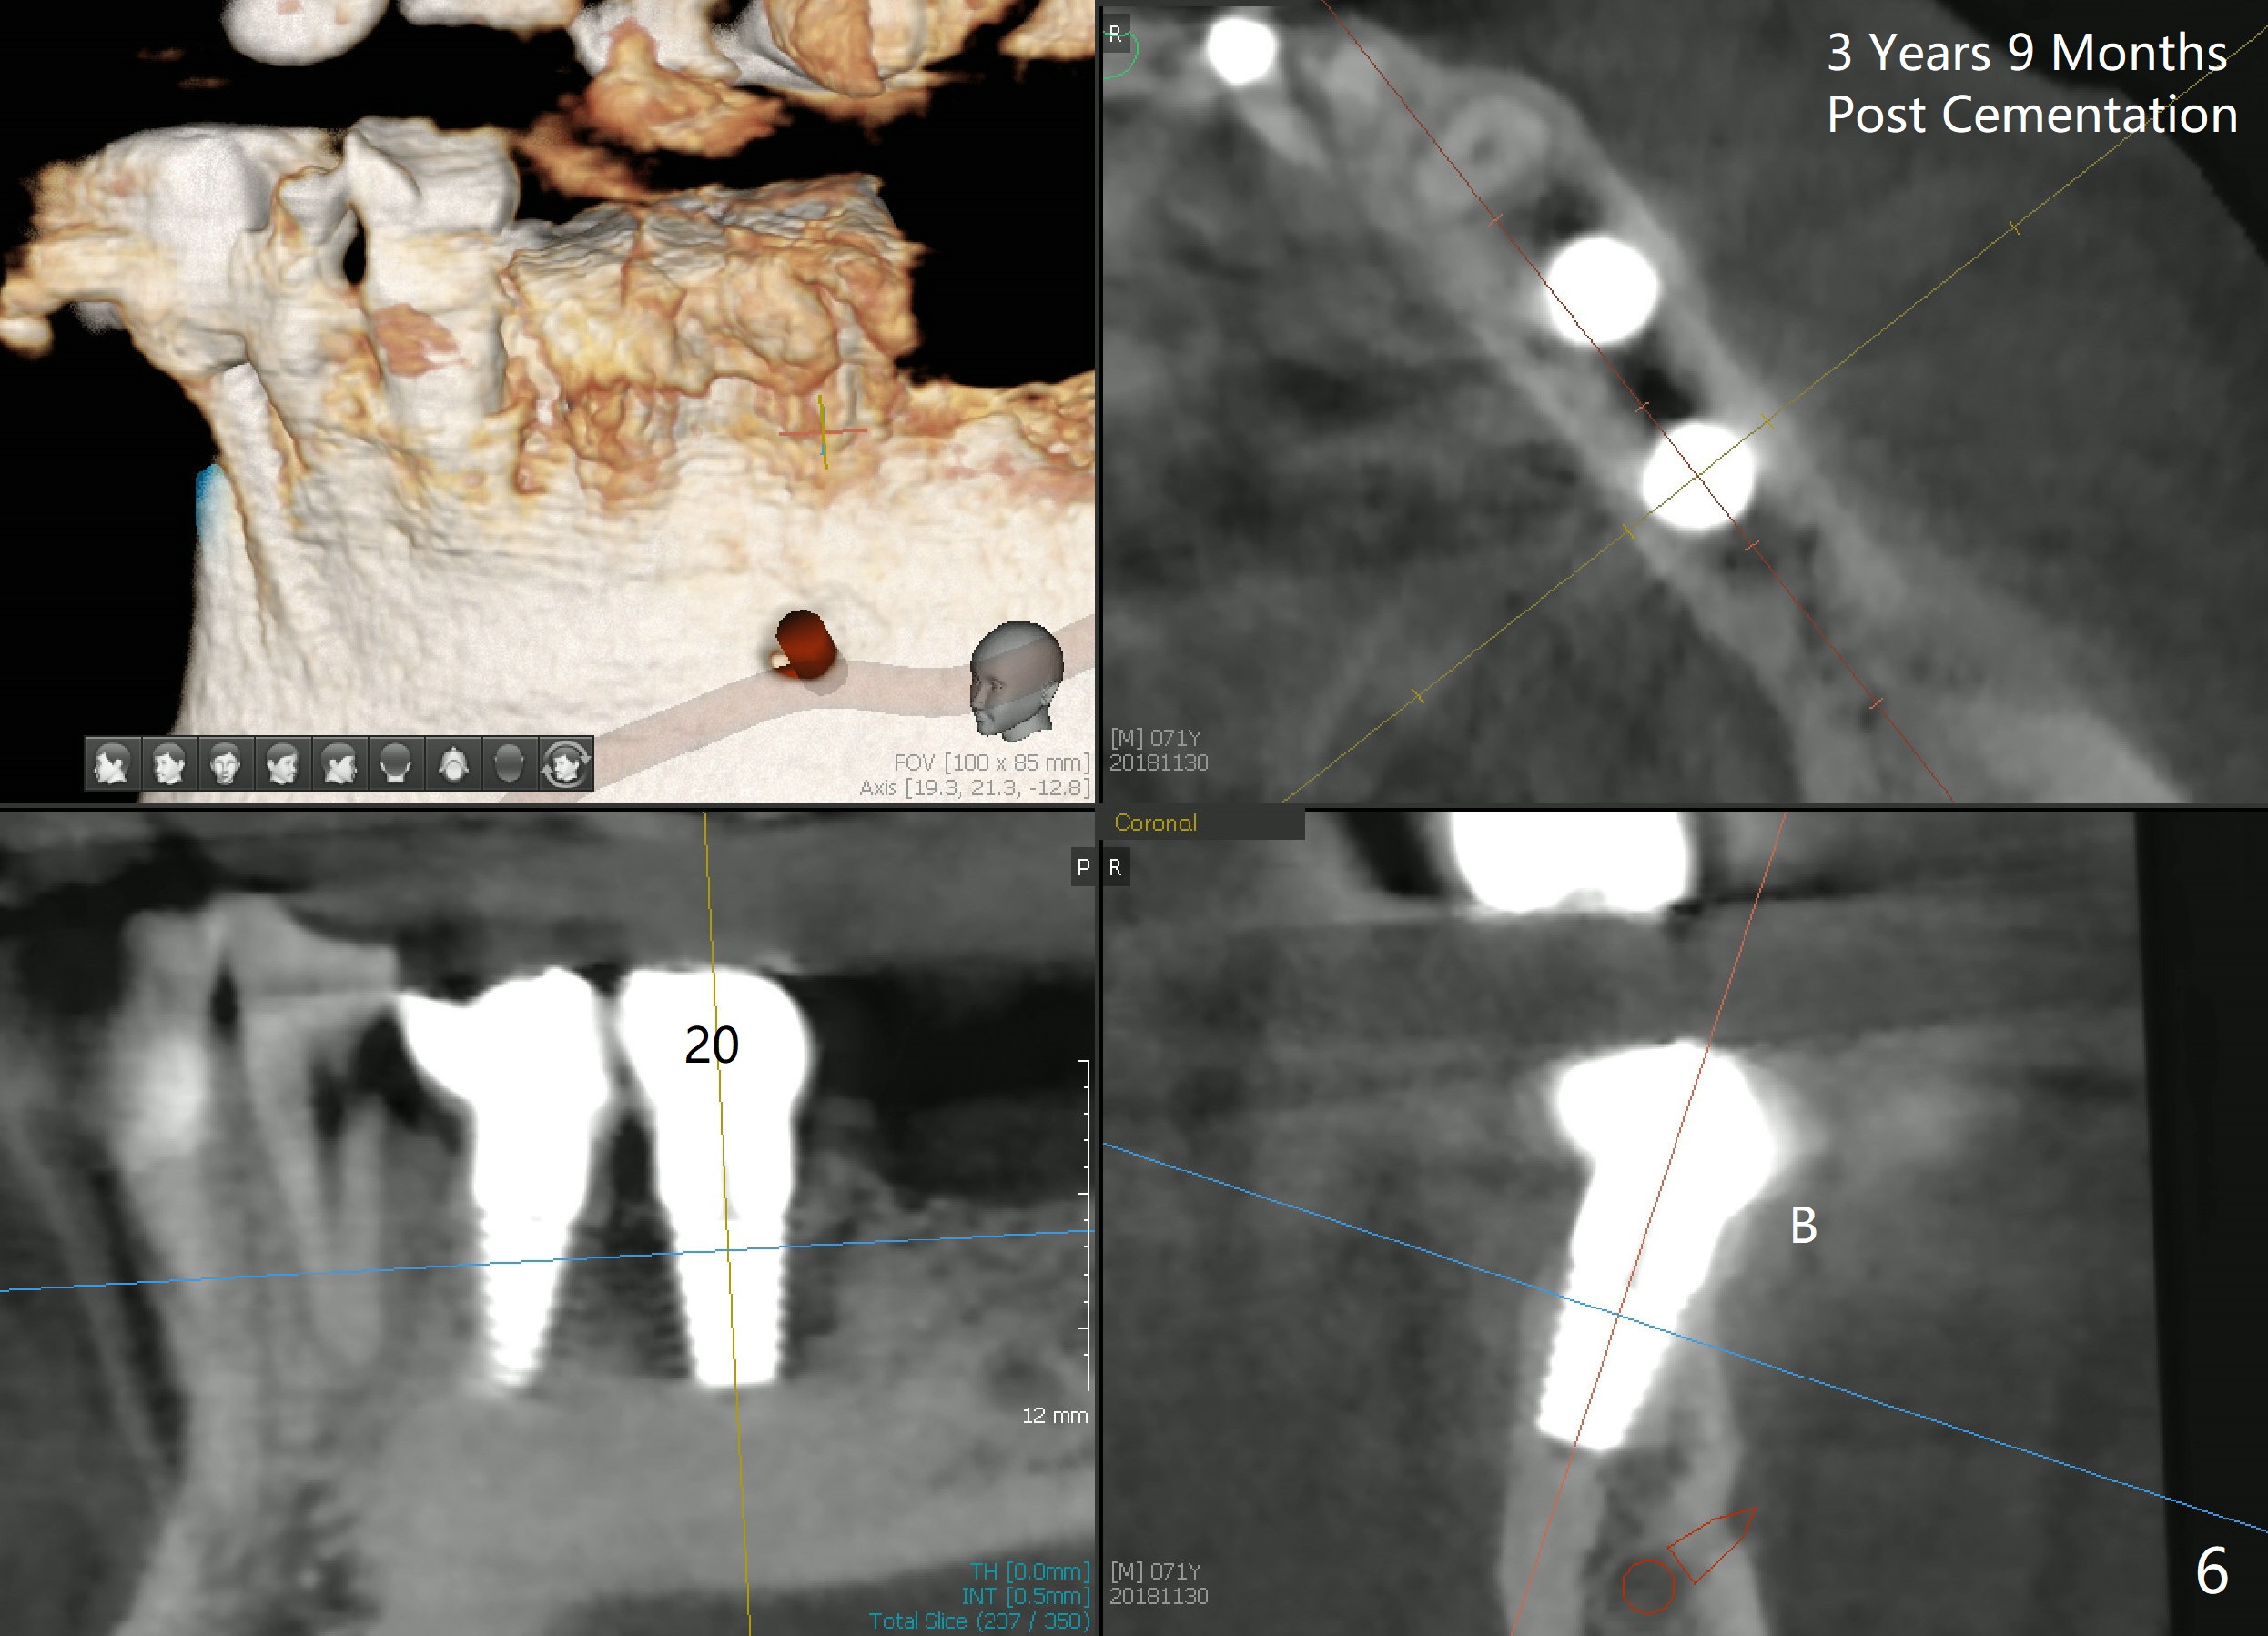

Two implants are to be placed at the sites of #20 and 21 (Fig.1 CT sagittal section) to be used as ortho anchorages. When paralleling pins (Fig.2 P) are inserted, they happen to be in the original sockets (arrowheads). Two 4.5x11 mm implants are also placed more or less in the original sockets (Fig.3). Postop X-ray is shown. Two separate provisional crowns are to be fabricated with the occlusal table of #20 being lower, since #13 has mobility and has supraerupted. Leave a space (1-2 mm) mesial to #21 provisional so that the tooth #22 and 23 can be moved distally. A premolar band is going to be placed at #21. There is no bone loss 2.5 years (Fig.4) or 3 years 9 months (Fig.5,6 CT) post cementation. Return to Implant & Ortho Full Mouth Reconstruction 3 24/26 28 30 Xin Wei, DDS, PhD, MS 1st edition 10/04/2014, last revision 12/16/2018